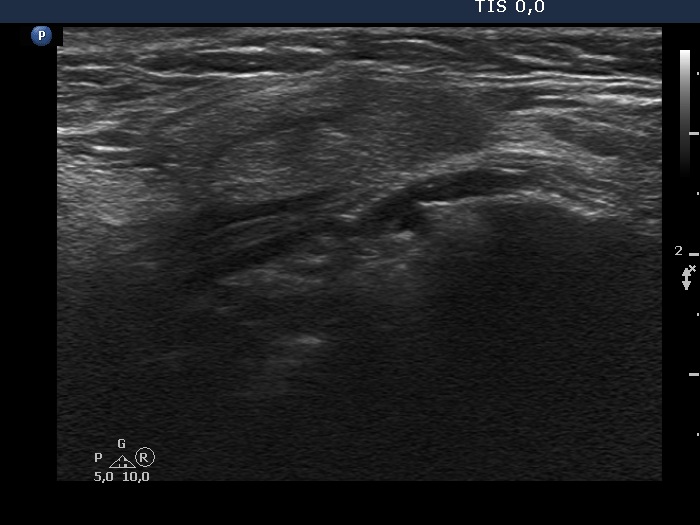

Case cons100_065 (ultrasonographic picture 2)

Right lobe, longitudinal view.